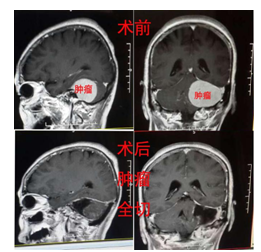

许某某,女性,70岁,因“头痛10天”收住入院,未见明显阳性体征,外院CT考虑左侧桥小脑占位病变,考虑脑膜瘤可能,入院后予手术治疗,术后病理回报提示:过渡型脑膜瘤WHOI型。

桥小脑角巨大脑膜瘤首选手术治疗,进入显微神经外科时代以来,手术治疗的目的不再仅仅是切除肿瘤延长病人生命,更加关注患者的生存质量,但影响手术效果的因素甚多, 如肿瘤直径、肿瘤质地、肿瘤血供丰富与否、肿瘤囊变与否、肿瘤生长方向、肿瘤与神经血管粘连程度、术中面神经监护与否等等, 更重要的是术者的经验。充分了解桥脑小脑角显微解剖知识, 特别是了解肿瘤与面神经的病理解剖关系有助于提高手术效果。如果手术残留,可以考虑辅助伽马刀治疗。